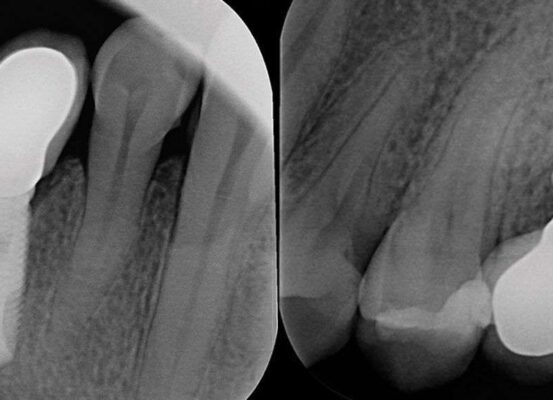

Paciente mujer de 14 años.Derivada de ortodoncia para extracción de un molar temporal retenido y del segundo premolar incluido (no pudo erupcionar por el molar temporal). Afortunadamente el primer pre